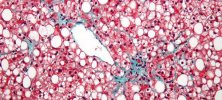

Naturalne białko zmniejsza masę tłuszczową aż o 1/3

29 października 2018, 13:00Białko FGFBP3 (BP3), które zespół z Georgetown University badał pod kątem nowotworów, okazało się silnym regulatorem metabolizmu. Wszystko wskazuje na to, że może odwracać zaburzenia związane z zespołem metabolicznym, np. cukrzycę typu 2. czy stłuszczenie wątroby.